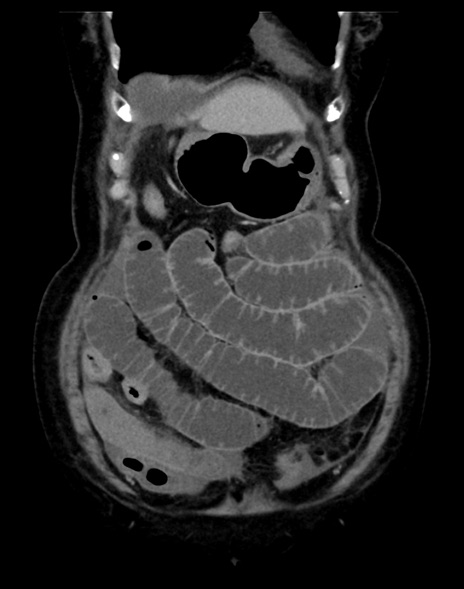

(横断像)1日半後